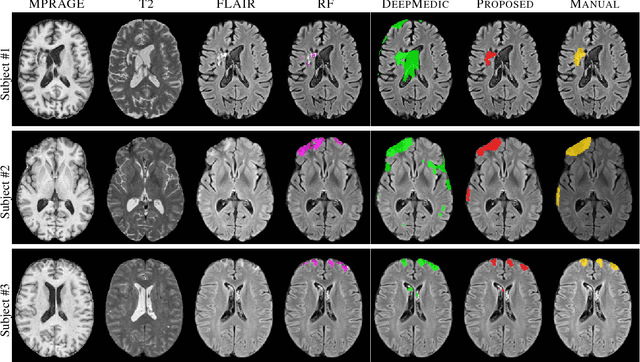

Abstract:Traumatic brain injury (TBI) is caused by a sudden trauma to the head that may result in hematomas and contusions and can lead to stroke or chronic disability. An accurate quantification of the lesion volumes and their locations is essential to understand the pathophysiology of TBI and its progression. In this paper, we propose a fully convolutional neural network (CNN) model to segment contusions and lesions from brain magnetic resonance (MR) images of patients with TBI. The CNN architecture proposed here was based on a state of the art CNN architecture from Google, called Inception. Using a 3-layer Inception network, lesions are segmented from multi-contrast MR images. When compared with two recent TBI lesion segmentation methods, one based on CNN (called DeepMedic) and another based on random forests, the proposed algorithm showed improved segmentation accuracy on images of 18 patients with mild to severe TBI. Using a leave-one-out cross validation, the proposed model achieved a median Dice of 0.75, which was significantly better (p<0.01) than the two competing methods.